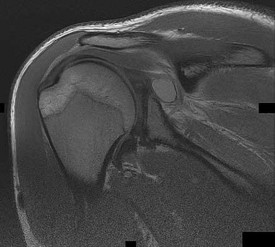

A 22-year-old rugby player with recurrent anterior shoulder instability and 25% glenoid bone loss undergoes a Latarjet procedure. This procedure restores stability through a described 'triple-blocking' effect. Which of the following mechanisms is considered the most significant dynamic contributor to anterior stability in the Latarjet procedure?

Options:

Correct Answer: The sling effect of the conjoined tendon reinforcing the inferior capsule and subscapularis when the arm is abducted and externally rotated

Explanation:

The Latarjet procedure provides a 'triple-blocking' effect for anterior shoulder instability. The three components are: 1) The dynamic 'sling' effect of the conjoined tendon across the inferior subscapularis and anterior capsule when the arm is abducted and externally rotated; 2) The static bony effect of the coracoid bone block increasing the glenoid arc; and 3) The capsular repair (capsule sutured to the CA ligament stump). Biomechanical studies have demonstrated that the dynamic sling effect of the conjoined tendon contributes most significantly to the stability provided by the construct, accounting for up to 75% of the stabilizing force.